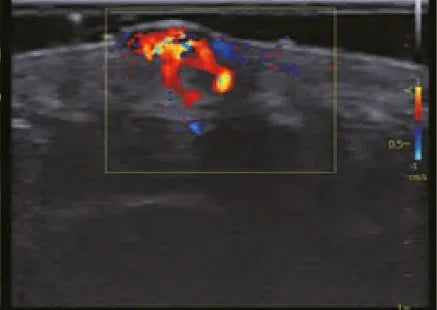

- Color Doppler , which differentiates the direction of blood flow using colors.

The principle is simple yet powerful: the device uses sound waves that bounce off red blood cells as they move within blood vessels. This change in frequency is what allows the speed and direction of the blood to be calculated.

- The screen displays color images or graphics showing blood flow in real time.